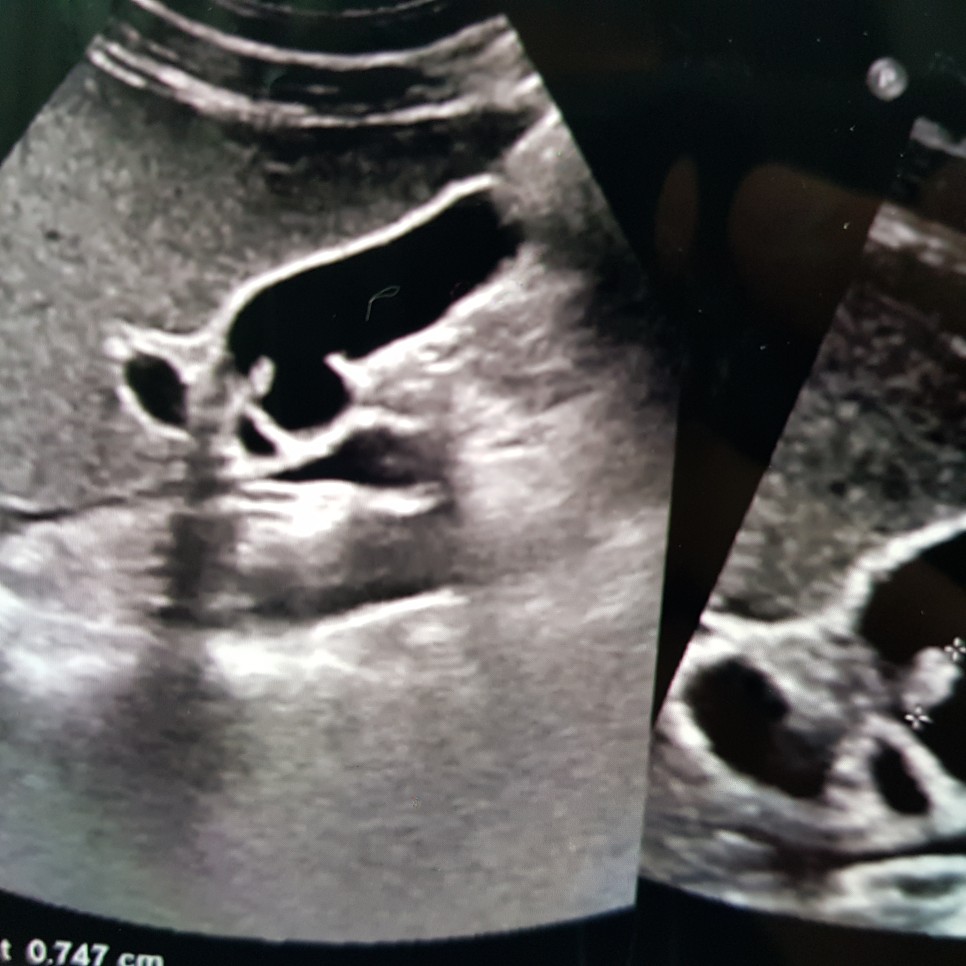

일단 증상이 의심되는 경우에는 서서 초음파 검사를 받는 진단 방법이 있다고 합니다

가끔 누워서 할 수도 있고, 오진의 가능성이 있다고 하며, CT 검사로 확인할 수도 있지만, 역시 누워서 진행하기 때문에 정확도가 부족한 것 같습니다.